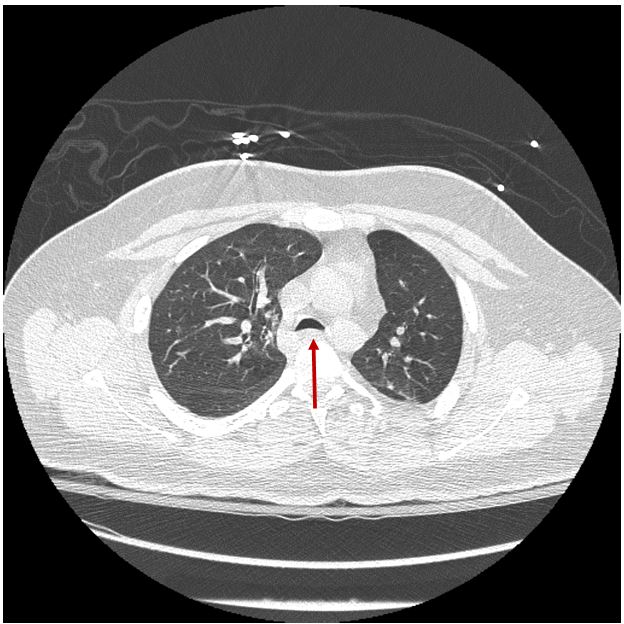

Figure 2.1 Computed Tomography (CT) of the chest showing decreased anterior-posterior diameter of the tracheal lumen